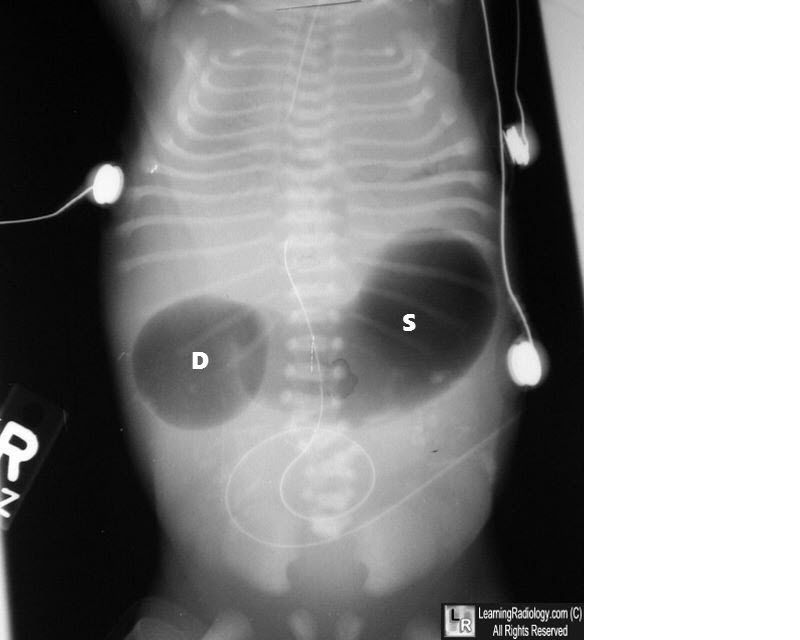

Double bubble sign is a radiographic finding. It is mostly found in adults. It refers to the proximal dilatation of duodenum secondary to obstruction and stomach. The differential diagnoses of double bubble sign are: - Duodenal atresia - Annular pancreas - Duodenal stenosis - Midgut volvulus - Retroperitoneal tumor - Preduodenal portal vein - Choledochal cyst - Mesenteric duplication cyst - Superior mesenteric artery syndrome - Intramural duodenal hematoma Reference: https://radiopaedia.org/articles/double-bubble-sign-duodenum Image via: https://learningradiology.com/notes/ginotes/doublebubblecorrect.html